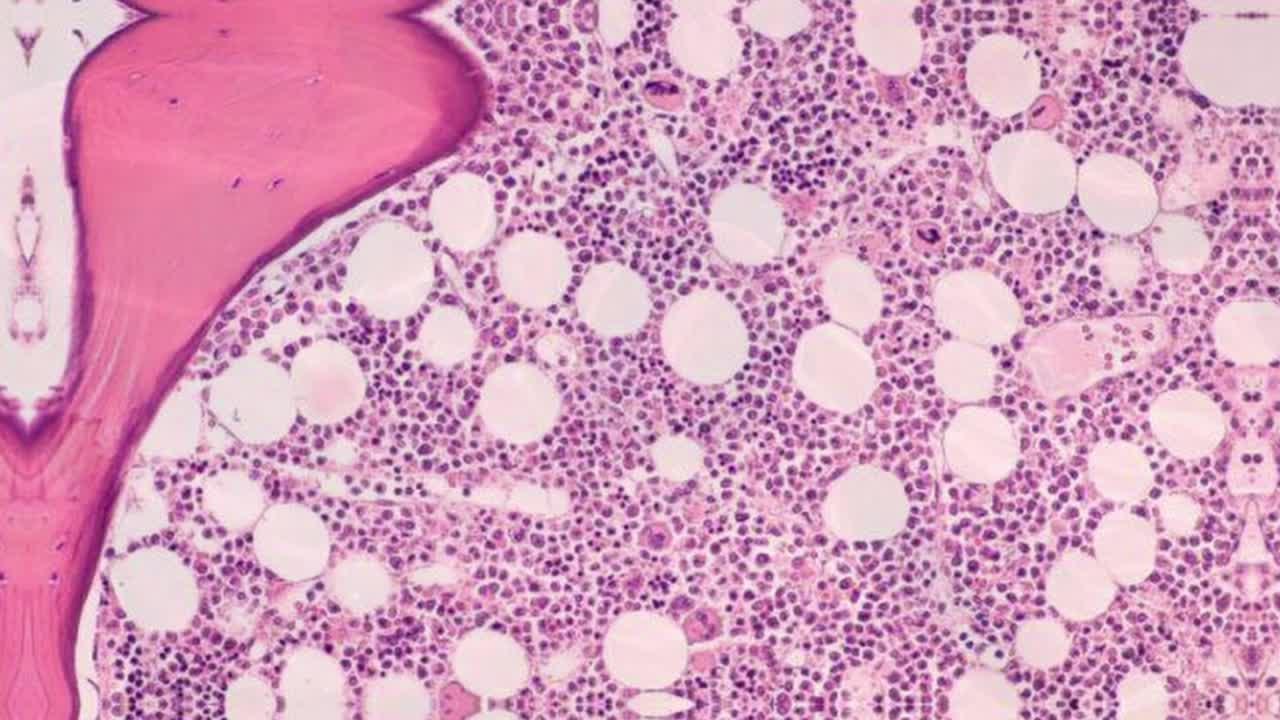

EL TEJIDO HEMATOPOYÉTICO (vídeo enriquecido)

¿De dónde viene la sangre? ¿Acaso la médula ósea es tan importante? Todas las preguntas que puedas hacerte sobre las células sanguíneas y este tejido ya han sido respondidas en este vídeo.